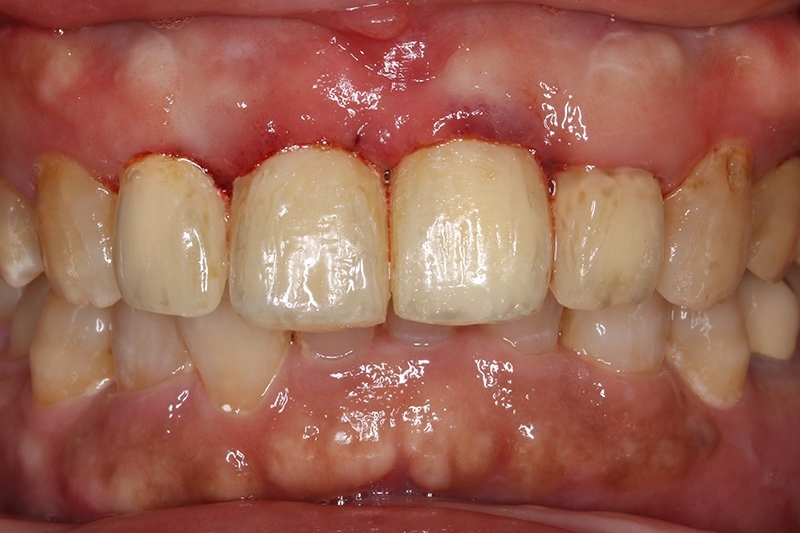

牙周治療前病患抱怨有膿在舊有的門牙植牙周邊,容易流血

經過牙周治療後,控制發炎,可見牙齦的狀況變得更健康了!